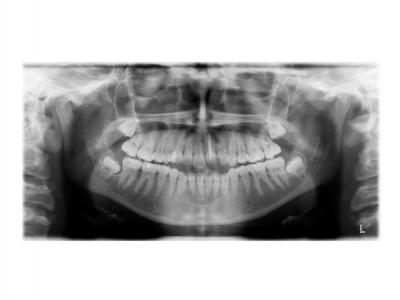

Dans le premier cas, la béance s'est fermée spontanément (pas prévu au départ) sans rééducation, sans appareil de contrainte linguale, ni élastique. Il semblerait que le gain de place a permis aux incisives de se redresser spontanément et donc de fermer la béance. La fermeture de la béance, la normalisation de l'environnement anatomique a permis à la langue de se mettre à travailler correctement. Pour le sens transversal, la correction a été aussi spontanée. Juste une minivis dans le secteur 1 a été placée pour recentrer mon milieu (ancrage maximal recherché au départ). Les finitions auraient pu être meilleures. Elle finit avec une légère classe II (on va dire qu’elle est surcorrigée :)). Le traitement a terminé plus tôt que prévu (24 mois annoncé), car problèmes de santé.

Dans le deuxième cas, le désencombrement a fermé les espaces en 6 mois. Les incisives ont été surtorquée pour avoir un meilleur soutien labial. Le traitement qui avait bien débuté, a été difficile à finir, car les anatomies coronaires et radiculaires étaient perturbées.

Si on n'avait pas extrait dans le premier cas, cela imposait une ouverture de l'espace de la 24 et donc une avancée des incisives supérieures et donc une aggravation de la béance. Dans le deuxième, on sortait les racines de l'os alvéolaires (racines déjà apparentes au départ). Même une expansion associée à du stripping et une distalisation des secteurs latéraux n’auraient pas permis de préserver ce parodonte fin.